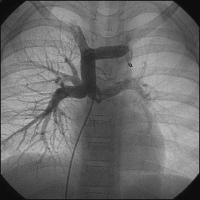

Die Fontan-Operation als definitive Palliation bei funktionell univentrikulären Herzen

Journal für Kardiologie - Austrian Journal of Cardiology 2012; 19 (11-12): 324-331 Volltext (PDF) Summary Fragen zum Artikel Abbildungen